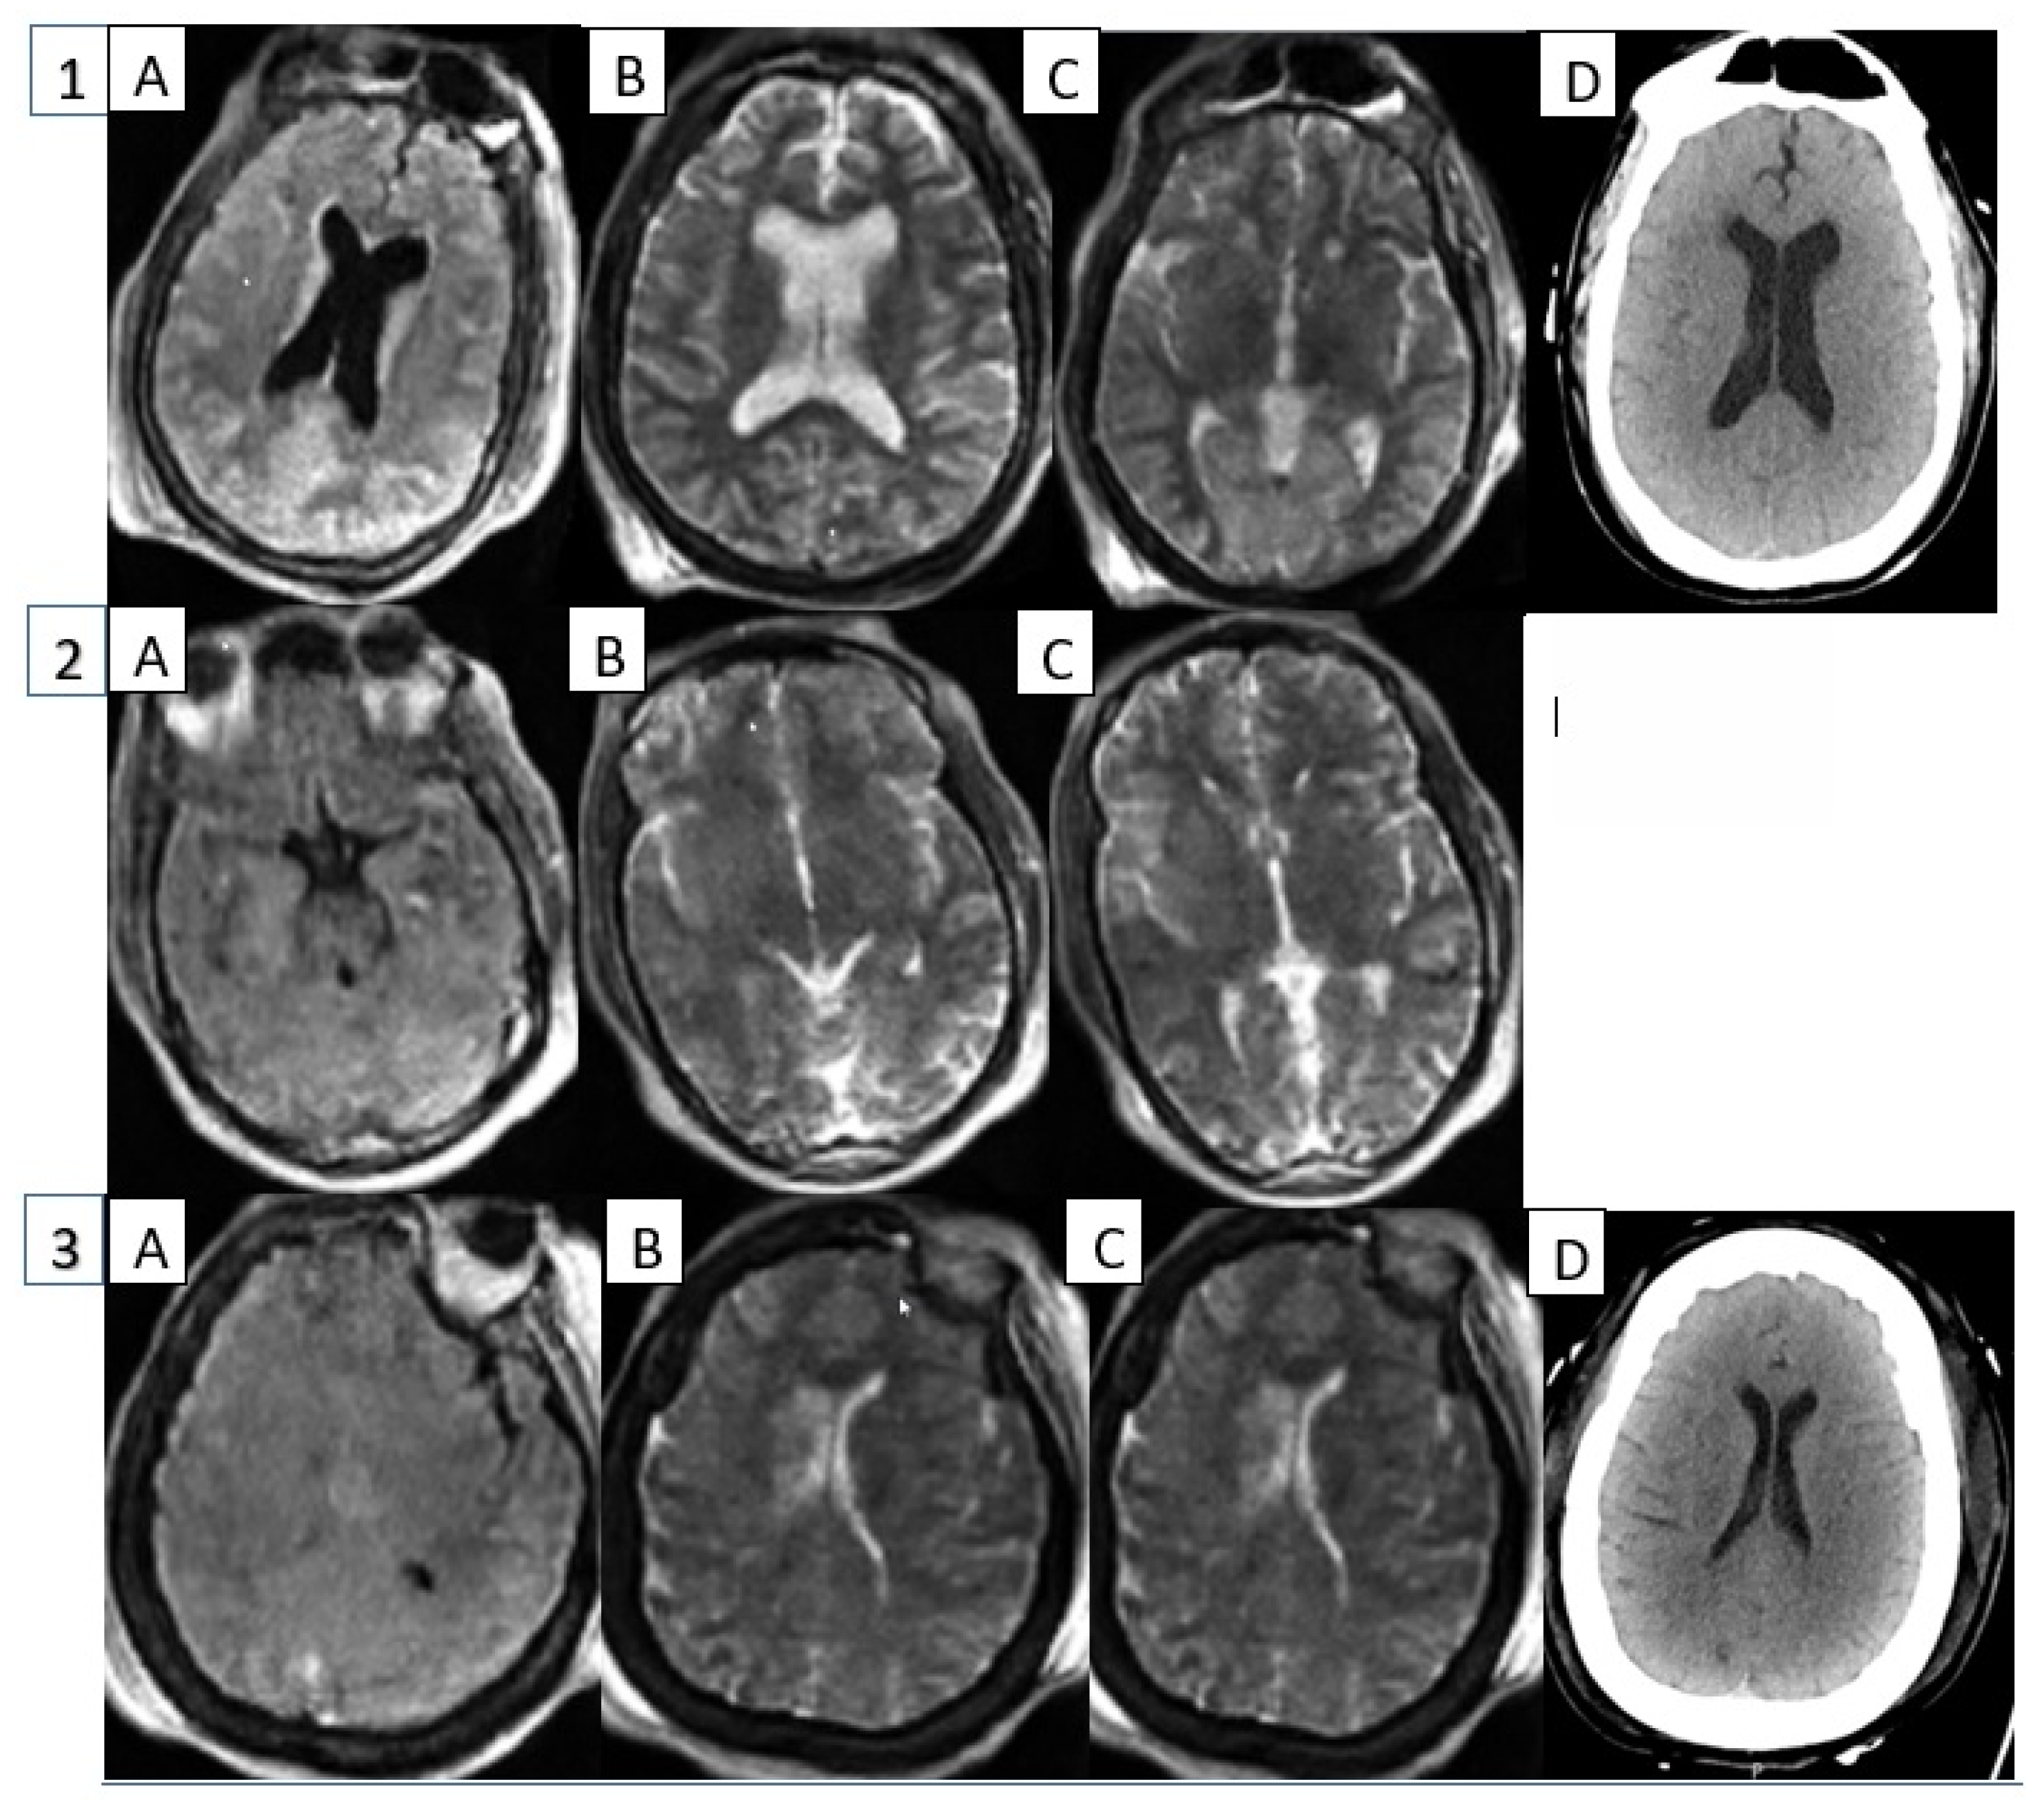

- Patient 1: A 72-year-old male with a past medical history of hypertension, diabetes, and end-stage renal disease that was cannulated on VA-ECMO via the right atrium and ascending aorta for post-cardiotomy shock. His cardiac function initially improved, and he was transitioned from VA-ECMO to IABP support after two days of VA-ECMO support. However, his cardiac function quickly deteriorated solely on IABP support, and he was placed back on VA-ECMO support in addition to IABP. He underwent his first HCT on day 2 of IABP (day 1 of ECMO) and was found to have global hypoxic ischemic brain injury and cerebral edema. A second HCT performed on day 4 of IABP (day 3 ECMO) had no changes from the prior HCT. POC MRI exams were performed immediately after each HCT, and both showed T2 signal abnormalities within the occipital lobes and left temporal and parietal lobes. For each POC MRI, the IABP was placed on a 1:2 rate, triggered with EKG waveform.

- Patient 2: A 37-year-old female with a past medical history of asthma, who was cannulated on VA-ECMO via the femoral vein and artery with IABP support for cardiogenic shock secondary to COVID-19 myocarditis. She underwent a POC brain MRI on day 2 of IABP (day 1 of ECMO), which showed focal encephalomalacia of the left cerebellar hemisphere. She did not undergo HCT imaging while on VA-ECMO and IABP support. During the POC MRI, the IABP was placed on a 1:1 rate, triggered with arterial pressure.

- Patient 3: A 71-year-old female with a past medical history of hypertension, diabetes, and chronic kidney disease who was cannulated on VA-ECMO via femoral vein and artery and IABP for post-cardiotomy shock. She underwent an HCT on day 1 of IABP (day 1 of ECMO), which was significant for age-indeterminate infarcts in the right thalamus and the right parietal and left occipital lobes. A subsequent POC brain MRI on day 4 of IABP (day 4 of ECMO) was without abnormalities. During the POC MRI, the IABP was paced on a 1:1 rate, triggered with EKG waveform.